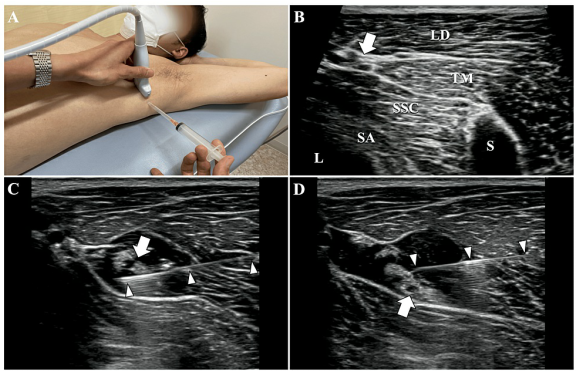

B,D 그림처럼 해당 검사에서 양성이라는 건, 어깨 관절의 아랫쪽과 뒷쪽이 꽉 조여져 있다는 것을 의미합니다. 정상적으로 팔을 들 때에는 어깨뼈와 팔뼈가 미끄러지듯이 움직여야 하는데, 관절이 꽉 조여 있으면이 중심축이 자꾸 틀어지게 됩니다. 이렇게 되면 팔을 올릴 때마다 SLAP 병변 위치에더 큰 압력이 가해지고,증상이 계속해서 악화되었던 것이죠. > 신경의 유착이 > > 어깨를 꽉 잡고 있다! 그렇다면 어깨 움직임을 제한하는 ‘꽉 조이는 느낌’은 어디에서 오는 걸까요? 연구진은 CAT와 HFT 검사 시 가장 심하게 늘어나는 신경을 주목했습니다. ◆ CAT (어깨 올림) 검사 시: 어깨 관절 아래쪽에 위치한 흉배신경 (Thoracodorsal Nerve, TDN)이 가장 늘어나고요. 광배근(Latissimus Dorsi) 등의 중요한 근육을 지배합니다. ◆ HFT (수평 모으기) 검사 시: 어깨 관절 뒤쪽에 위치한 액와신경 (Axillary Nerve, AxN)이 가장 늘어나고, 소원근(Teres Minor)과 같은 근육을 지배합니다. 이 사례에서는 이 두가지 신경 주변 조직이염증으로 인해 유착되면서어깨의 가동 범위를 제한하고, 결과적으로 SLAP 병변의 통증을 유발했다고 가설을 세웠습니다. 즉, 구조적인 문제가 아니라 신경 포착 증후군이 통증의 원인일 수 있다는 새로운 관점이죠. > 관절경 수술이 아닌 > > 비수술 치료 그래서 선택한 치료법이 바로 ‘하이드로다이섹션(Nerve Hydrodissection)’, 즉 신경 박리술입니다.  DOI: 10.7759/cureus.60157 1. 흉배신경 (TDN) 치료: 환자는 눕거나 엎드린 자세에서 진행됩니다. 광배근(LD), 대원근(TM), 견갑하근(SSC) 사이를 지나는 흉배동맥을 이정표(landmark) 삼아 신경 다발을 찾아냅니다. 이곳에 약침을 정밀하게 주입하여, 신경과 주변 유착된 조직 사이를 부드럽게 분리시키고요.

DOI: 10.7759/cureus.60157 1. 흉배신경 (TDN) 치료: 환자는 눕거나 엎드린 자세에서 진행됩니다. 광배근(LD), 대원근(TM), 견갑하근(SSC) 사이를 지나는 흉배동맥을 이정표(landmark) 삼아 신경 다발을 찾아냅니다. 이곳에 약침을 정밀하게 주입하여, 신경과 주변 유착된 조직 사이를 부드럽게 분리시키고요.  2. 액와신경 (AxN) 치료: 다음은 옆으로 누운 자세에서 액와신경을 찾습니다. 액와동맥을 이정표 삼아 상완골두(HH), 대원근(TM), 소원근(Tm), 상완삼두근 장두(LTB)로 형성된 곳을 지나는 액와신경 다발을 확인합니다. 역시 초음파로 실시간 확인하면서 신경과 주변 조직을 떼어놓습니다. 이러한 치료는 유착된 신경의 움직임과 기능을 개선하고, 신경 주변의 국소 혈액 순환을 증진시켜서 신경에서 오는 통증을 완화하는 데 효과적입니다. > 결과는? > > 관절와순 파열 관절염 어깨 통증 치료 흉배신경에 시술 직후, 앞서 양성이었던 CAT 검사가 정상이 되었고, 액와신경 시술 직후에는 HFT 검사 역시 호전되었습니다. *즉각적으로